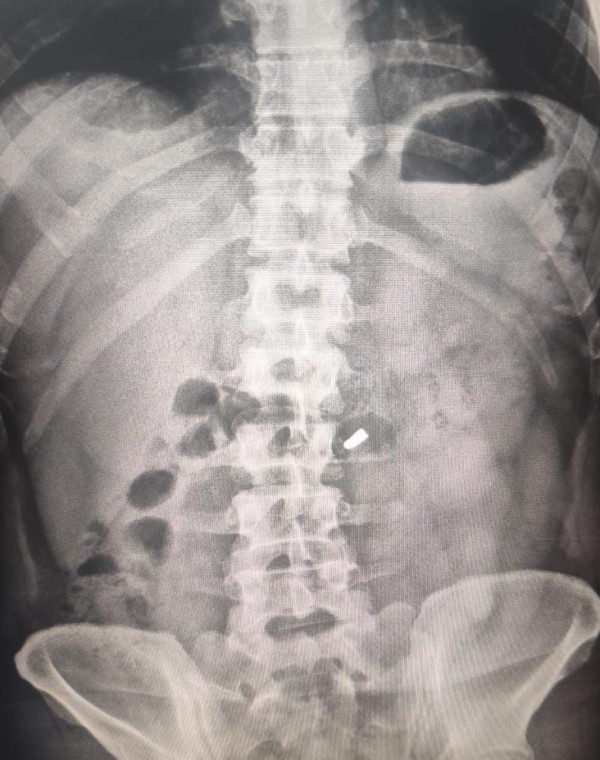

Pese a la herida, el vecino se negó a recibir asistencia médica en el lugar y se trasladó por sus propios medios al Hospital Vicente López y Planes. Allí, tras realizarle estudios, los médicos constataron que tenía un proyectil alojado en el abdomen lateral derecho, con orificio de entrada, aunque sin compromiso vital.

Foto: Güemes Informa.